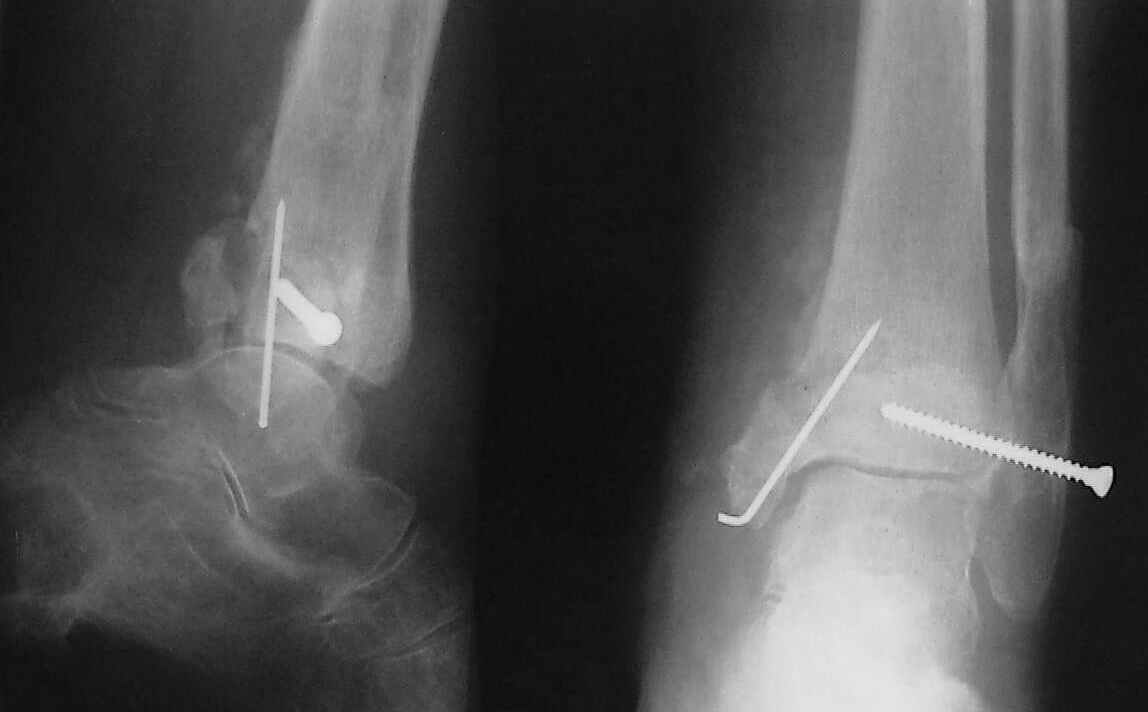

Больная 1936 г.,травма 15 ноября 2003,закрытый трехлодыжечный перелом г/стопного сустава, сахарный диабет.

При поступлении - закрытая репозиция, повторная в связи с большим отеком через неделю, подготовлена к остеосинтезу в первых числах декабря. Заживление без осложнений. Циркулярный гипс - 7 недель, снят,часть спиц удалено 20 февраля т.к.пальпировались под кожей, постепенная нагрузка, проблем нет до середины апреля когда появильсь боли с мед. стороны сустава и локалная гиперемия ( трактовалась как флеботромбоз). Повторное поступление 15 апреля - усиление болей,пов. температура, локально выраженная гиперемия.Локально выделений нет. На RTG - деструкция в области мед лодыжки и заднего края. Сахар крови умеренно повышен. Как трактовать проблему, какой диагноз и тактика лечения? Заранее спасибо, Владимир.

Диагноз я бы поставил: неправильно срастающийся перелом обеих лодыжек и заднего края ББК. Ложный сустав мед. лодыжки? Хронический вялотекущий остеоимиелит голеностопа. Сопутствующий - СД, диабетическая ангиопатия 2.

Ретроспективно, на Ваш взгляд, что изменилось бы при остеосинтезе более массивными имплантами?(выбор в пользу спиц как раз и был из-за минимального объема оставляемых имплантов) Иммобилизация 7 недель это очень длительно? Результат на 4 RTG - в чем нефункциональность? - согласен, что репозиция заднего края не была достигнута. Какие признаки ложного сустава мед. лодыжки ?

Уважаемый Владимир. Нестабильность и нефункциональность, как мне видится по снимочкам, была изначально,об этом ниже В чём вы видите массивность третьтрубчатой, например титановой 1.5 мм пластины? Ими оперируют во всём мире и получают хорошие результаты, а почему у нас это массивно мне непонятно.Спицевая "тюрьма" хороший способ, но только для временной интраоперационной фиксации, хотя лично я редко пользуюсь, на то есть костодержатели для малых фрагментов и репонирующие винты. Кстати в данном случае, при её остеопорозе лучше было бы поставить LCP (опуская финансовую сторону вопроса, в теории). А вот функциональность - при правильном подборе и установке металлоконструкций пациент нуждается в иммобилизации на срок заживления швов, а уж потом ходьба без нагрузки на оперированную конечность 6 недель - (базовый курс АО). Ретроспективно, как мне видится, при хорошей репозиции и фиксации всё бы консолидировалось, хотя на всё воля божья, но по крайней мере не нужно было бы удалять железки. Иногда ставишь всё как мама родила, а потом очень плохие последствия. Признаки ложного (?) я вижу на снимках,хотя это может быть и банальное отсутствие консолидации за столь длительный срок, что само по себе я бы расценил как ложный сустав. А что Вы сами думаете по этому поводу? И как планируете артродезировать? (если планируете). Мне кажется, самое обидное то, что и эндопротез голеностопного поставить там просто некуда. Я бы думал об очень сомнительном прогнозе.

На остеомиелит/гнойный артрит не очень похоже, больше на трофические расстройства. Попробовать бы что-то из нестероидных противовоспалительных. Конечно, еще и на фоне коррекции гликемии.

По стихании обострения - артродез голеностопного сустава был бы окончательной операций, обеспечивающей опорную и безболезненную конечность. Мы бы сделали L-образным доступом параллельно переднему контуру наружной лодыжки с уходом кзади, с пересечением малоберцовой кости вверху раны и отворотом единого кожно-костного лоскута, с последующей продольной остеотомией малоберцовой кости для обнажения губчатой кости; такой доступ дает очень хороший обзор суставных поверхностей таранной и большеберцовой костей для сятия хрящевого покрова. Фиксация аппаратом из двух опор - по паре спиц в таранной и

большеберцовой костях, наружную лодыжку прижать спицей с упором (лучше в виде петли) к продольному пазу, сформированному по латеральной поверхности сочленяющихся костей.